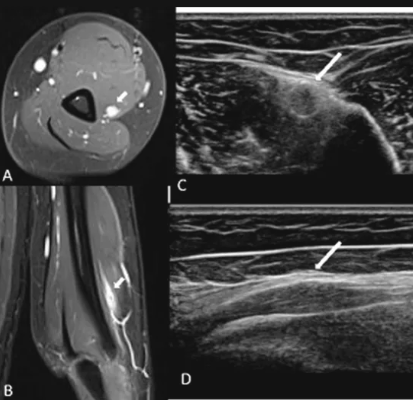

신경전도 검사와 근전도 검사(EMG)를 통해 요골신경 기능의 손상 여부 및 정도 확인

원인을 제외하기 위해 필요할 경우 영상 검사(MRI 등) 시행